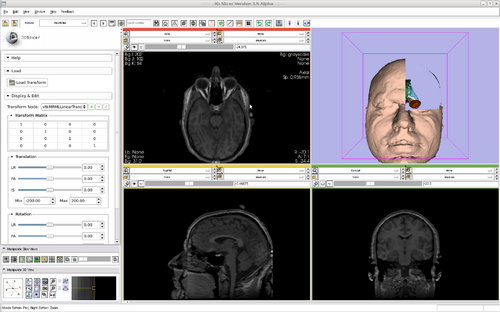

Slicer

Modules